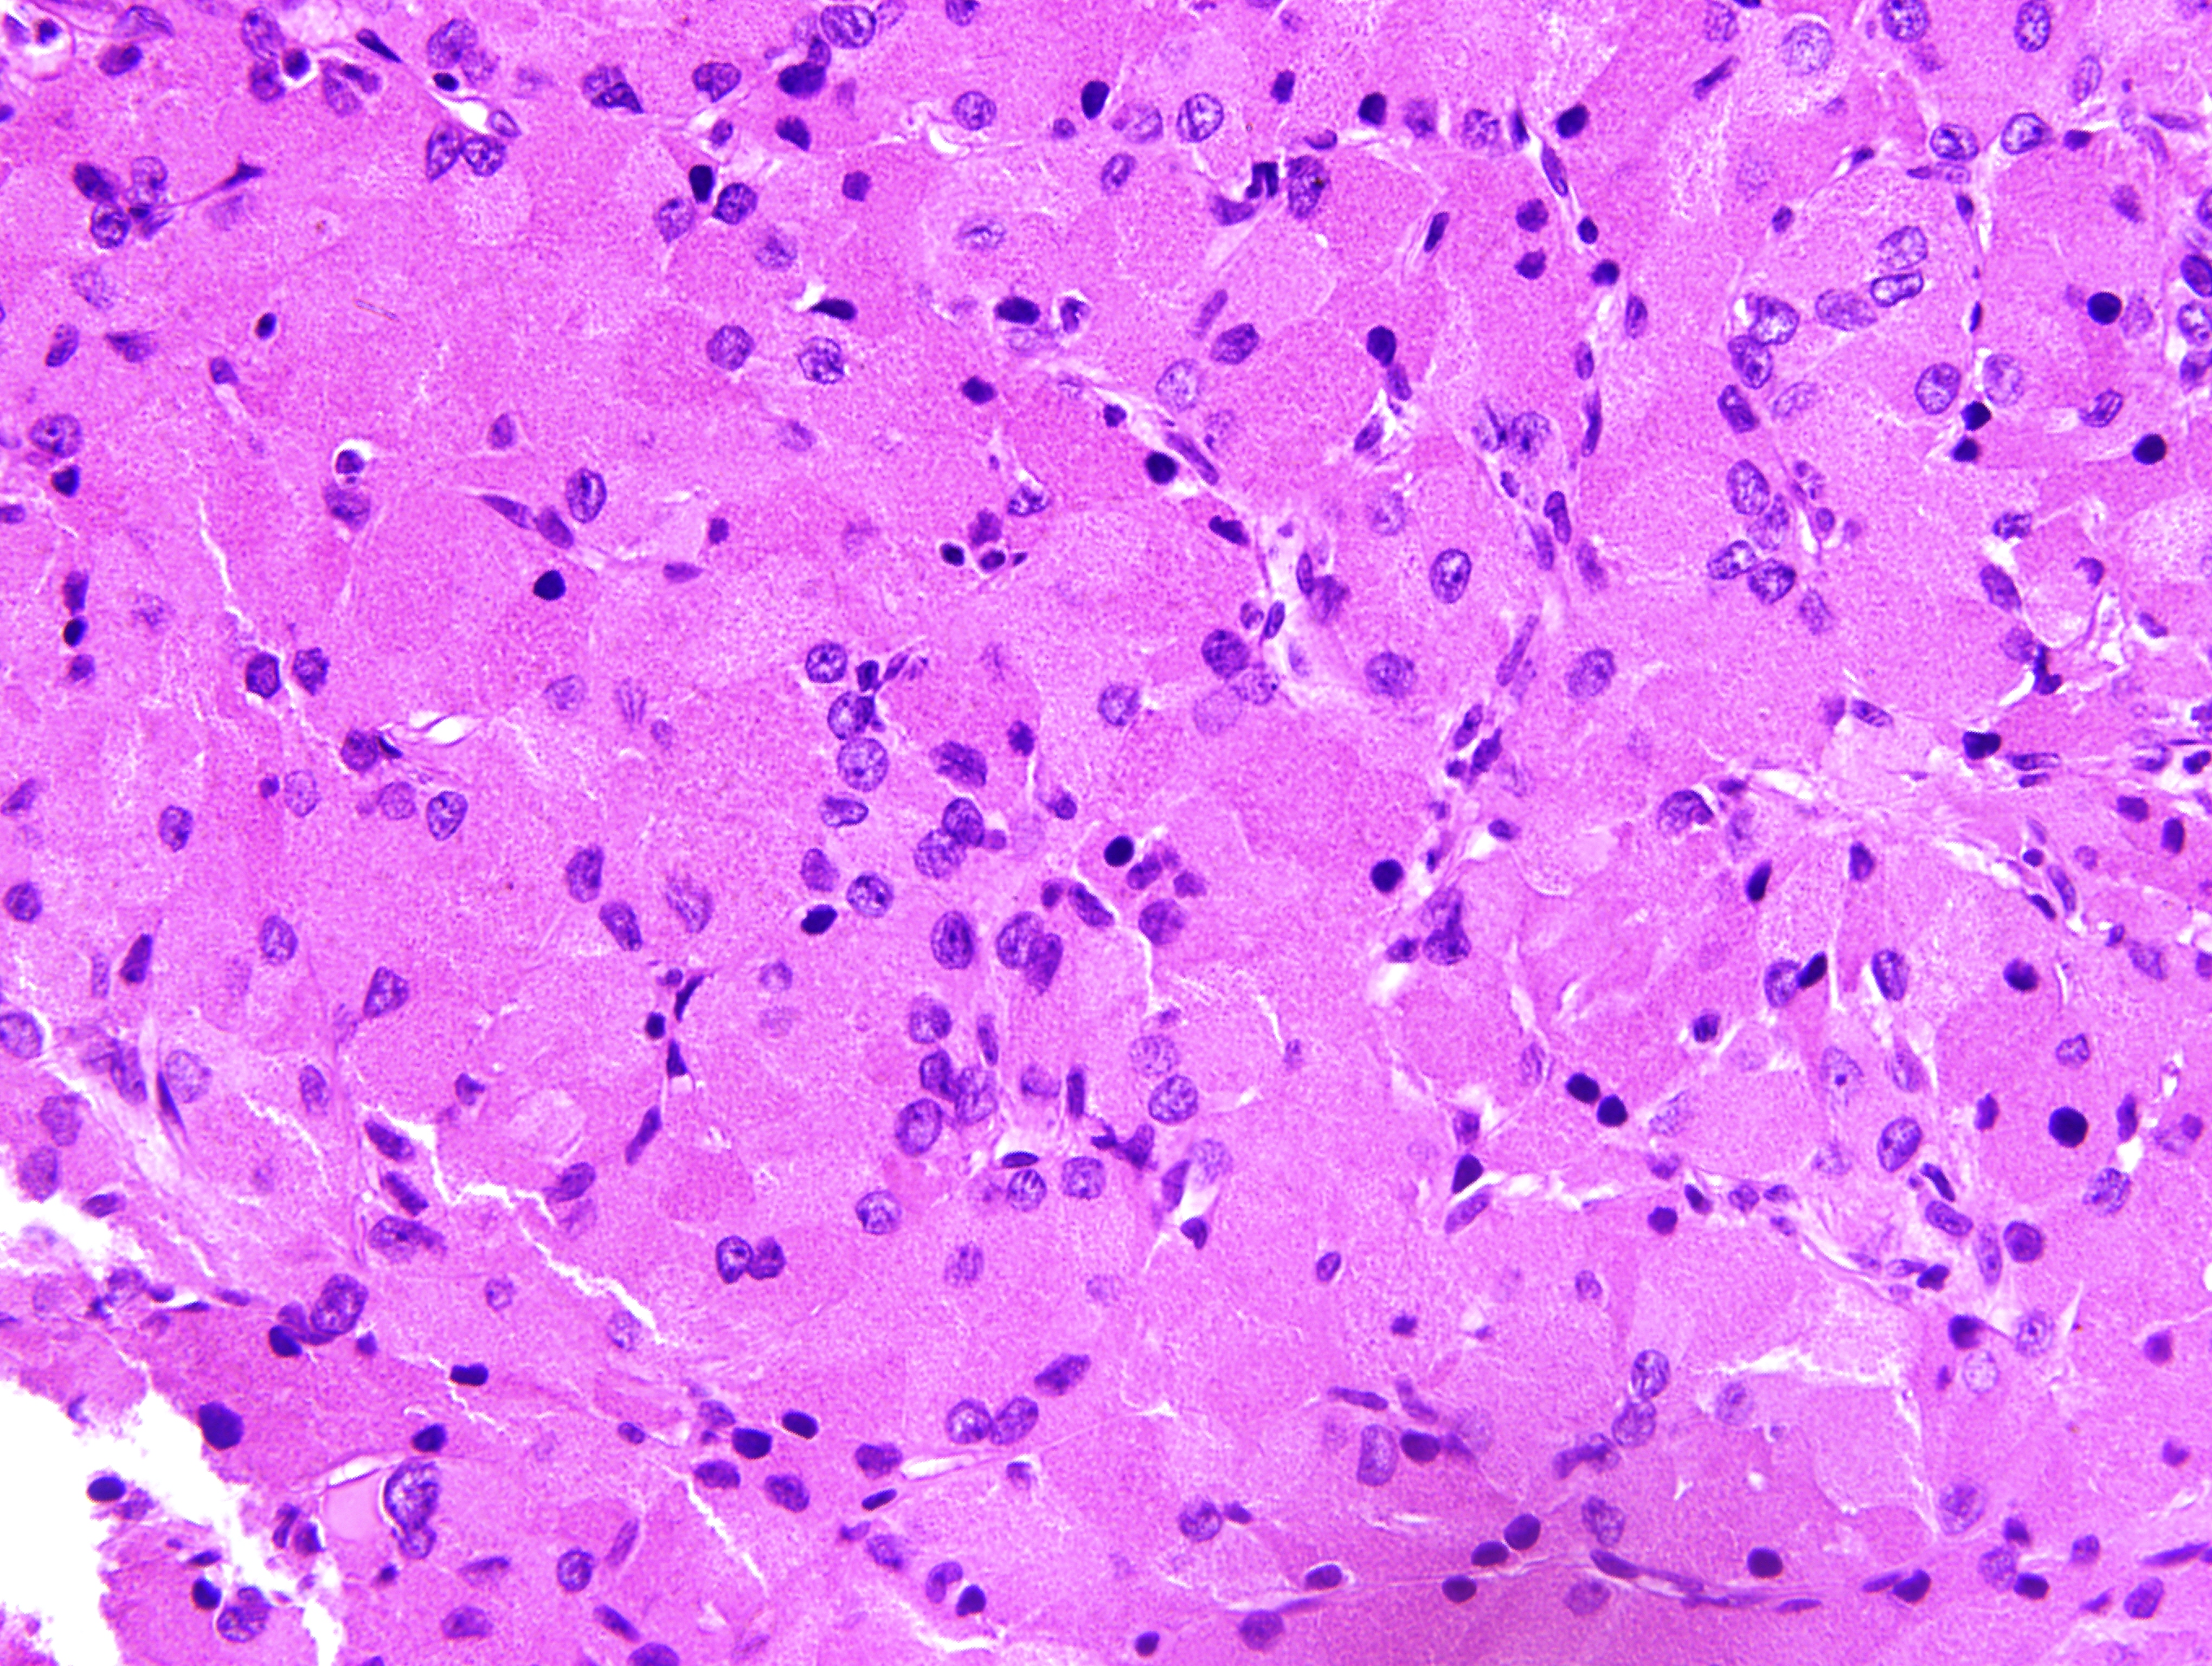

3. hematoxilina y eosina

| Asunto | |

| Tipo | Instrumentación |

| Ver (5MB) Indexación de metadatos |